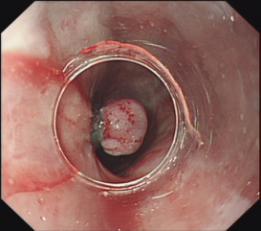

胆石症ERCP治疗